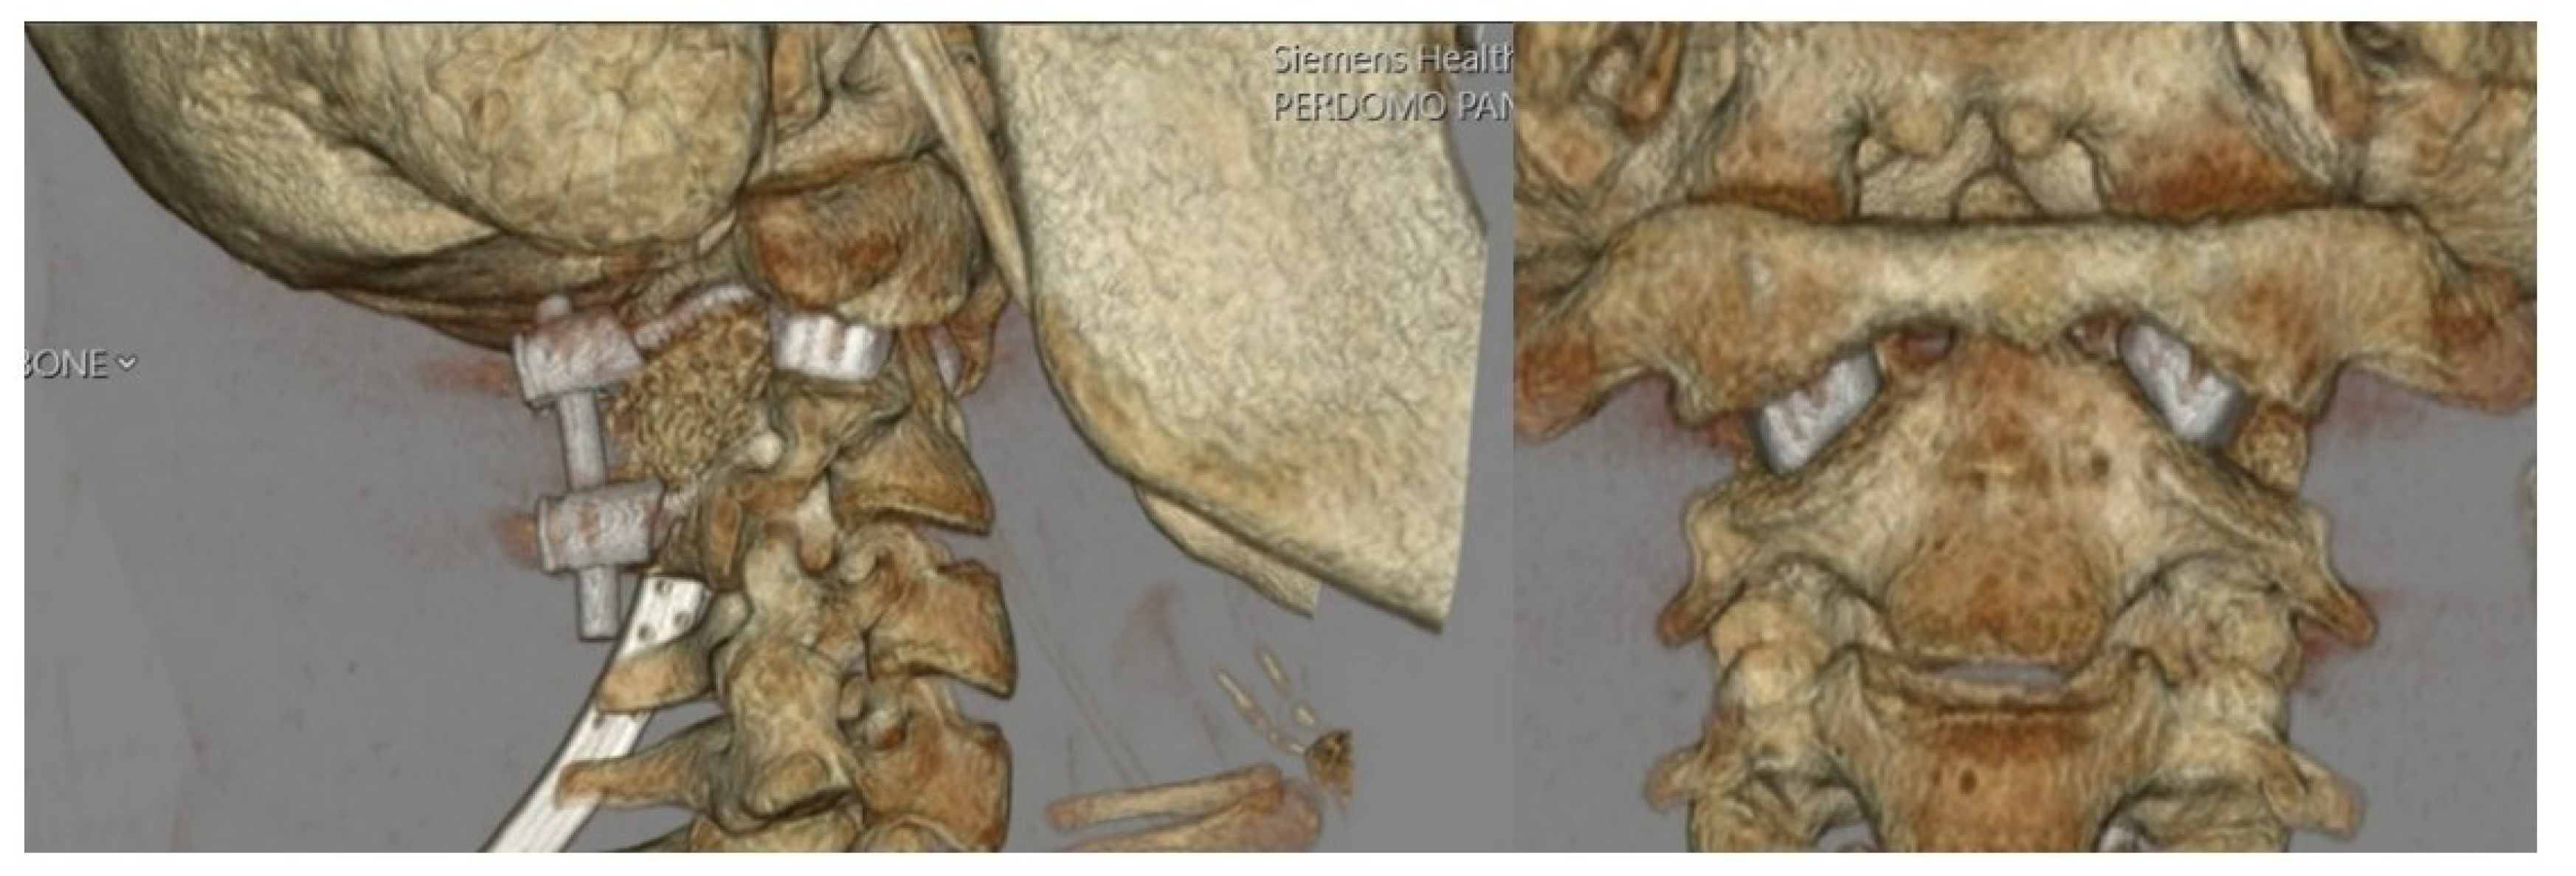

3.1. Preoperative Planning and 3DPI Design

4. Results